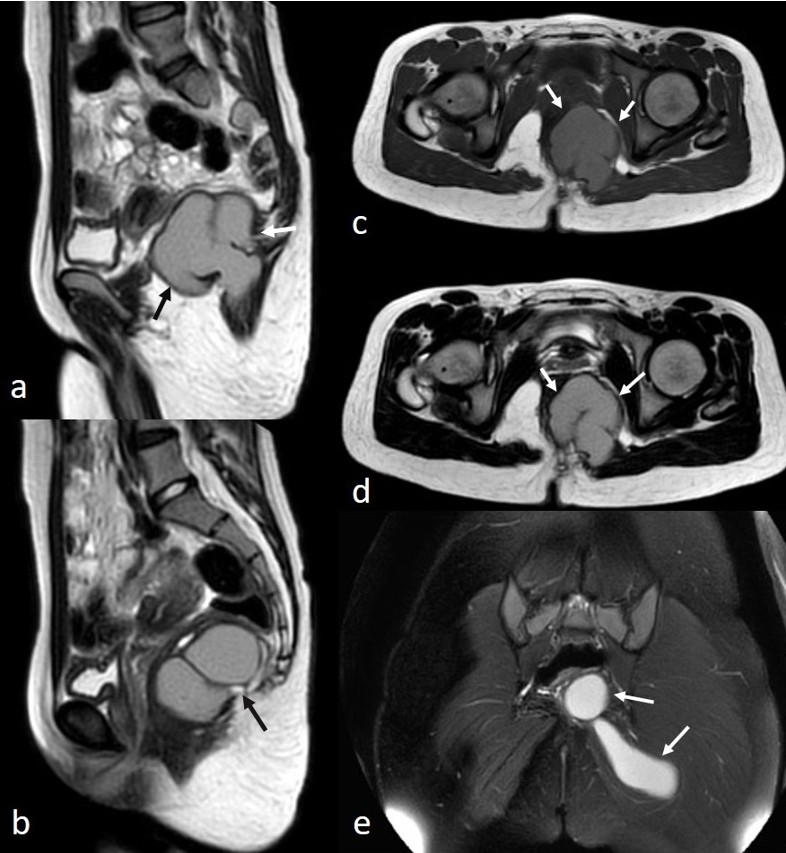

A suprapubic pelvic ultrasound revealed a septated cystic lesion measuring 7.5 x 6.5 cm, located posterior to the uterus and left ovary. The uterus and ovaries appeared normal in size and morphology. Magnetic resonance imaging (MRI) demonstrated a cystic lesion extending from the left perianal area to the left gluteal region. The lesion appeared iso- to hyperintense on T1-weighted images and hyperintense on T2-weighted images, with thick material and a lobulated contour. The gluteal extension measured approximately 8 cm in length. No edematous signal changes, effusion, or perianal fistula suggestive of inflammation were observed (Fig. 1). The lesion showed diffusion restriction and exhibited peripheral contrast enhancement (Fig. 2).

The abscess culture showed no bacterial growth, but cytological analysis of the drainage fluid revealed abundant parasitic oocytes consistent with E. vermicularis, along with inflammatory cells. The lesion was diagnosed as a parasitic abscess, and the patient received pyrantel pamoate at 11 mg/kg/day for three days. Esophagogastroscopy and colonoscopy revealed mild hyperemia and increased vascularisation of the rectosigmoid colon, with no evidence of inflammatory bowel disease. Pathologic evaluation of the endoscopic biopsies showed lymphoid hyperplasia and edema-congestion, but no eosinophilia was reported. On the one-month postoperative follow-up MRI, the gluteal component was completely drained, with a small residual perirectal component observed, which continues to be monitored following medical treatment. Written informed consent was obtained from the patient and her parents for this report and accompanying images.

In our case, the lack of surrounding inflammatory changes made a bacterial abscess or infected perirectal mass less likely. Well-defined margins, as well as high intensity on T1-weighted images, suggested perianal cysts, such as teratomas and tailgut cysts, as potential differential diagnoses. However, diffusion restriction and thick enhancing walls, consistent with perianal abscess formation, led to diagnostic uncertainty. There was no evidence of perianal fistula. The final cytological diagnosis of parasitic abscess confirmed that the iso-hyperintense appearance on T1-weighted images was due to the thick pus content of the abscess.